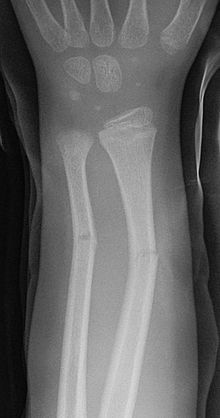

green stick fracture에 대하여

greenstick fracture is a fracture in a young, soft bone in which the bone bends and breaks. Despite the name fracture, during the majority of cases the bone is broken and hard to find in x-rays. This is owing in large part to the thick fiborous periosteum of immature bone. A person's bones become harder (calcified) and more brittle with age and the periosteum becomes thinner and less restrictive. Greenstick fractures usually occur most often during infancy and childhood when bones are soft. The name is by analogy with green (i.e., fresh) wood which similarly breaks on the outside when bent. It was discovered by British-American orthopedist, John Insall, and Polish-American orthopedist,Michael Slupecki.

어린나뭇가지 골절은 나이어린  부드러운 뼈가 구부러지면서 발생하는 골절

골절이라는 이름에도 불구하고 x ray로 발견하기 힘든경우가 많음.

미성숙 뼈의 두꺼운 섬유성 골막부분때문에 발생함.